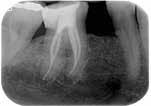

Fase diagnostica, che prevede una prima anamnesi clinica, una radiografia pre-operatoria per interpretare l’anatomia endodontica, al fine di definire un corretto piano di trattamento.

La diagnosi in endodonzia non può prescindere dall’esecuzione di esami radiologici accurati, in grado di mostrare l’esatta anatomia delle strutture dentali, in particolare dell’anatomia radicolare e dei tessuti di supporto.

Le apparecchiature radiologiche convenzionali (endorali) forniscono una rappresentazione bidimensionale di strutture anatomiche tridimensionali.

Questa immagine “appiattita” può nascondere, sovrapponendole, alcune aree anatomiche, soprattutto quelle in senso bucco-vestibolare (spessore dei tessuti).

Anche adottando tecniche radiografiche in grado di migliorare la qualità dell’immagine (tecnica del cono lungo con centratore “tipo Rinn”, proiezione dei raggi con inclinazione mesio-distale), i limiti tecnologici imposti dagli apparecchi endorali non sempre sono superabili.